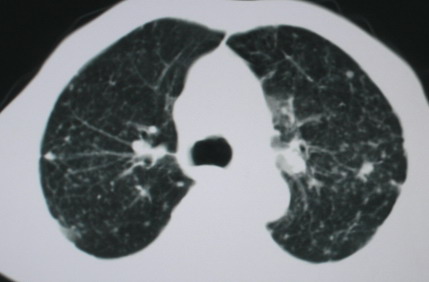

以下是引用卜一在2008-6-3 19:33:00的发言:[br]双肺结节,以双上肺分布为多,期间搀杂片状致密影及索条致密影。考虑:继发性肺结核伴血型播散可能性大。不除外肺泡ca的可能!另:椎体退变!

以下是引用panyishengct在2008-6-3 21:09:00的发言:[br]双上肺弥漫性小结节影,纵隔窗内钙化淋巴结影,考虑矽肺或/和tb可能性较大,不除外肺ca可能。腰椎考虑退变。 [br][br]